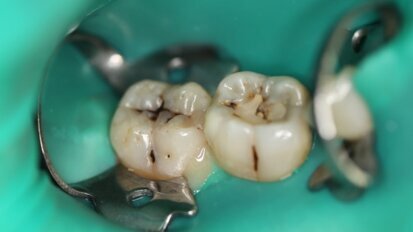

Leczenie próchnicy laserem Er:YAG zgodnie z koncepcją terapii minimalnie inwazyjnej

Współczesne standardy postępowania terapeutycznego w stomatologii zachowawczej zmierzają w kierunku procedur małoinwazyjnych. Obecny stan wiedzy ...